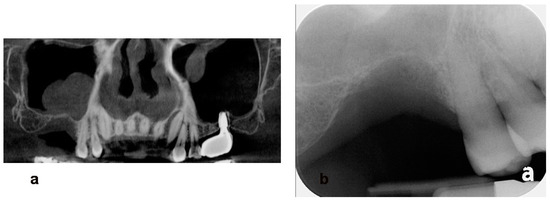

- Woo, R.H.; Kim, H.G.; Kim, G.; Park, W.E.; Sohn, D.S. Simplified 3-dimensional ridge augmentation using a tenting abutment. Adv. Dent. Oral. Health 2020, 12, 185–205. [Google Scholar]

- Sohn, D.S. Reconstruction of three-dimensional alveolar ridge defects utilizing screws and implant abutments for the tent-pole grafting’ techniques. In Essential Techniques of Alveolar Bone Augmentation in Implant Dentistry, 2nd ed.; Tolstunov, L., Ed.; Wiley Blackwell: Hoboken, NJ, USA, 2023; pp. 404–418. [Google Scholar]